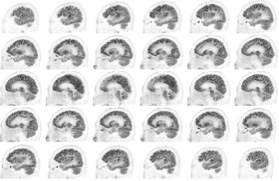

Head / Case2 : FDG

Sagittal

Courtesy : Kindai University Hospital

- Imaging protocol

- Injected dose: 3.29 MBq/kg, 18F-FDG

- Uptake time: 38 minutes

- Scan time: 30 minutes